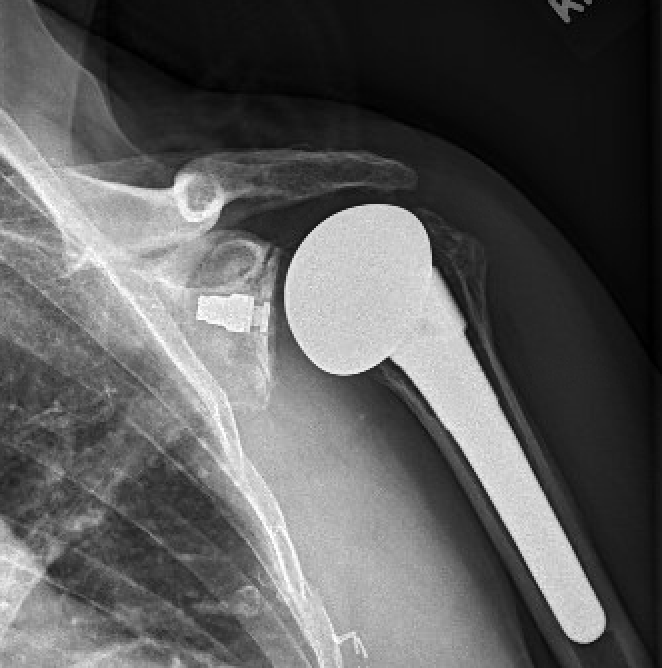

Four recently published articles provide important new information about the ream and run procedure for active patients with shoulder arthritis Those readers interested in learning more can access a discussion of these new articles here: shoulderarthritis.blogspot.com/2026/03/cocr-r…